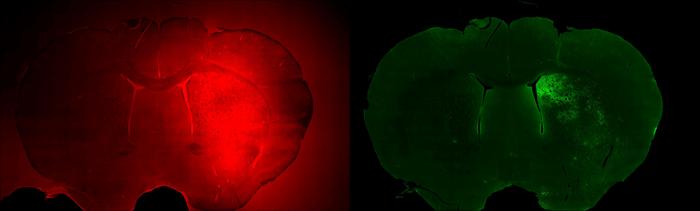

CAPTION: Striatum region (left) in rodent brain with opened blood-brain barrier. Green fluorescent protein expressed in striatum region in rodent brain (right) in response to induced neuronal activity. (Image courtesy of Laboratory for Noninvasive Imaging/Rice University)